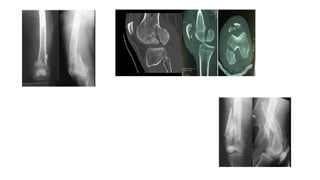

• Diagnosis

• Pain

• Swelling

• Bruising around the

knee

• Difficulty walking

• X-ray

• Thigh with Knee –AP &

Lateral

• Thigh with hip- AP &